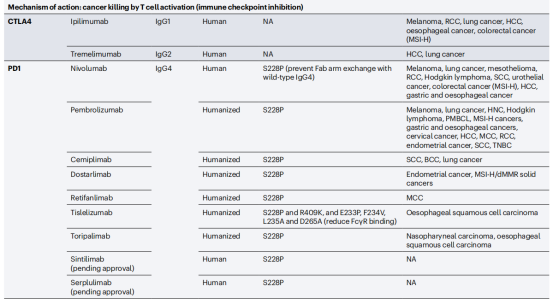

免疫检查点抑制剂:针对免疫细胞调节检查点的单特异性抗体在癌症患者中显示出了显著的临床疗效。FDA和EMA批准的11种免疫检查点抑制抗体目前正在用于治疗20多种不同类型的癌症,包括肺癌、黑色素瘤、肾细胞癌、头颈部鳞状细胞癌,预计还有几种这些抑制性抗体将在不久的将来获得批准。

免疫检查点通过阻断抗体抑制负调节T细胞的途径,从而使细胞毒性T细胞重新活化,杀死癌细胞。已获得FDA或EMA批准的治疗性抗体靶向的三种蛋白或途径是CTLA4,PD1-PDL1和LAG3。PD1阻断抗体是目前使用最广泛的免疫检查点抑制剂。7种已获批的PD1阻断抗体和目前正在临床试验的两种使用IgG4格式,与IgG1同型相比,它不能有效激活补体级联,Fc受体结合较弱。因此,IgG4格式可能保护表达PD1的效应T细胞不被ADCC或CDC无意中杀死。所有IgG4抗体都携带S228P突变以防止Fab臂交换。通过结果生物学分析发现,PD1的2种阻断抗体pembrolizumab和nivolumab结合PD1的不同表位,并且与配体PDL1结合位点重叠,从而阻止PD1-PDL1相互作用。PDL1靶向抗体与PDL1和PDL2复合物的晶体结构鉴定了PDL2中一个关键残基(Trp100),该残基阻碍抗PDL1抗体与PDL2的结合,并提供了PDL1和PDL2之间的选择性机制。

两种CTLA4靶向抗体Ipilimumab和Tremeli-mumab具有相似的结合表位,可以有效地与天然配体CD80和CD86竞争。